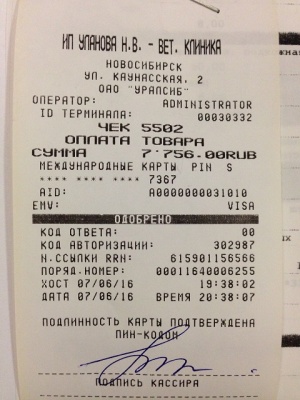

– окончательная оплата за проведение компьютерной томографии правого скакательного сустава (КТ) врач Горшков Сергей Сергеевич, и операции (снятие пластины) хирург Козлов Евгений Матвеевич, клиника Бэст (чек 3, товарный чек 3, лист назначений – документ 3) – 7756 руб.;

– окончательная оплата за проведение компьютерной томографии правого скакательного сустава (КТ) врач Горшков Сергей Сергеевич, и операции (снятие пластины) хирург Козлов Евгений Матвеевич, клиника Бэст (чек 3, товарный чек 3, лист назначений – документ 3) – 7756 руб.;